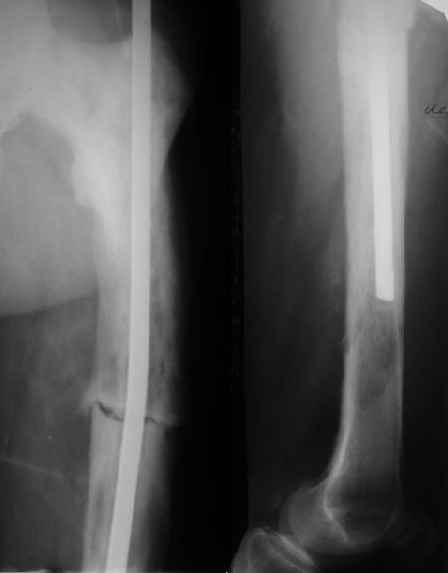

Пациент 82 лет, поступил через 5 мес. с несросшимся переломом после открытого интрамедуллярного остеосинтеза. Выполнили реостеосинтез стержнем 12 мм. ( мах. доступного нам в 2003 г.) Через 4 мес динамизация. В течении 2х лет сращения нет, тем не менее конечность опорна (ходит с тростью). От очередного реостеосинтеза отказались из-за сопутств. патологии.

Еще один пример. Пациентка с юга России, прислала рентгенограммы через год. На сегодня прошло 2 г. 8 мес. после операции. Несмотря на не очень убедительный процесс сращения, пациентка ходит. Учитывая остеопороз при Педжете, решили, что динамизировать вообще не нужно.